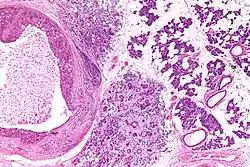

Low magnification micrograph of a salivary duct carcinoma with characteristic comedonecrosis (left of image) adjacent to normal parotid gland (right of image). H&E stain.

Salivary duct carcinoma (SDC) is a rare type of aggressive cancer that arises from the salivary glands.[1] It is predominantly seen in men and, generally, has a poor prognosis.[2] Other high grade carcinomas can mimic SDC. About 40-60% of SDC arise in pleomorphic adenomas.[3] Most, if not all, SDCs express androgen receptor by immunohistochemistry.[4] Therapeutically relevant genetic alterations include ERBB2/Her2 amplification, PIK3CA and/or HRAS mutations.[5][6]

SDC are diagnosed by examination of tissue, e.g. a biopsy.

Their histologic appearance is similar to ductal breast carcinoma.